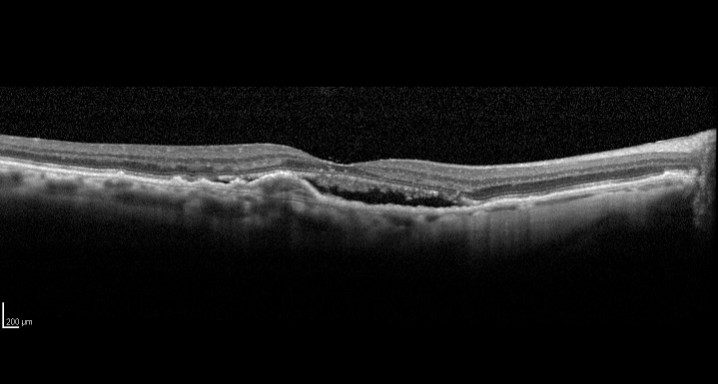

MACBETH. Ensayo clínico en fase IV para evaluar la eficacia de aflibercept en pacientes con degeneración macular asociada a la edad (DMAE) neovascular, sin respuesta óptima a repetidas inyecciones mensuales intravitreas de anti VEGF-A 19/03/2014

Ensayo clínico en fase IV para evaluar la eficacia de aflibercept en pacientes con degeneración macular asociada a la edad (DMAE) neovascular, sin respuesta óptima a repetidas inyecciones mensuales intravitreas de anti VEGF-A. MACBETH.